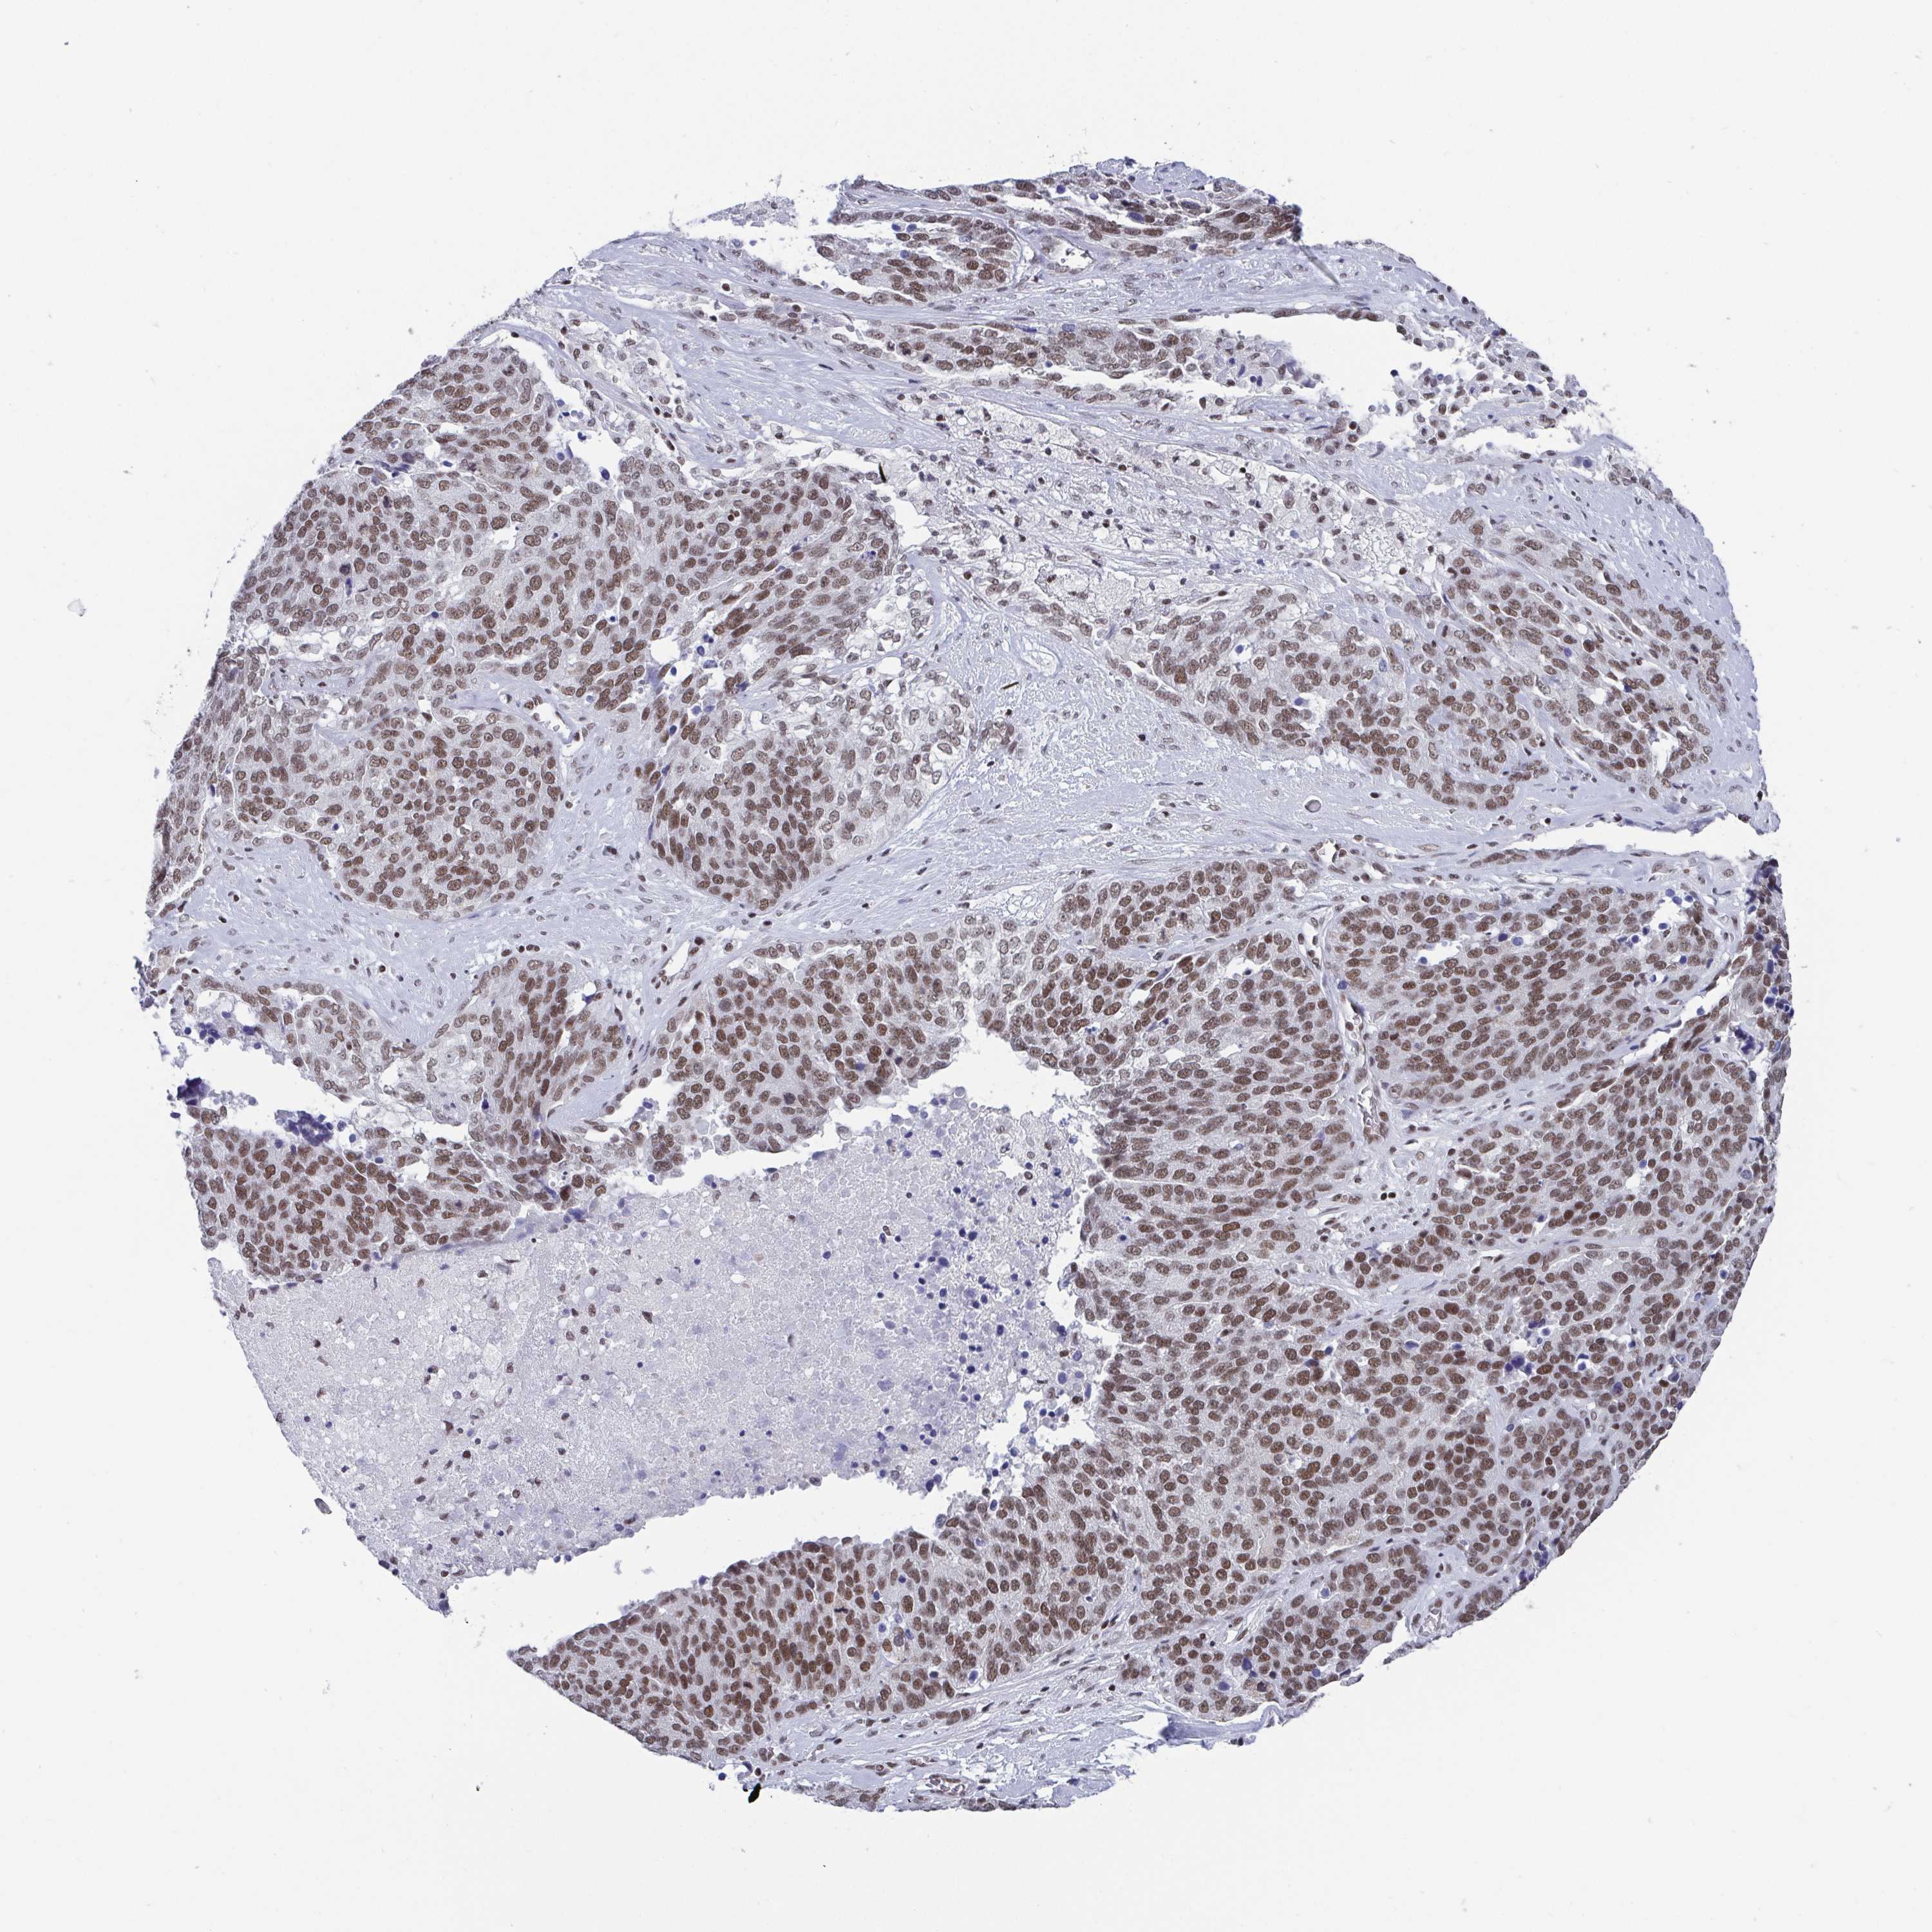

OVARIAN CANCER - Protein expressioni

A mouse-over function shows sample information and annotation data. Click on an image to view it in a full screen mode. Samples can be filtered based on level of antibody staining by selecting one or several of the following categories: high, medium, low and not detected. The assay and annotation is described here.

Note that samples used for immunohistochemistry by the Human Protein Atlas do not correspond to samples in the TCGA dataset.

Antibody stainingi

Antibody staining in the annotated cell types in the current human tissue is reported as not detected, low, medium, or high, based on conventional immunohistochemistry profiling in selected tissues. This score is based on the combination of the staining intensity and fraction of stained cells.

Each image is clickable and will lead to virtual microscopy that enables deeper exploration of all samples and also displays staining intensity scores, fraction scores and subcellular localization as well as patient and tissue information for each sample.

Antibody HPA004122

Antibody CAB062550

Antibody CAB068181

Antibody CAB068182

Staining

High

Medium

Low

Not detected

Intensity

Strong

Moderate

Weak

Negative

Quantity

>75%

75%-25%

<25%

None

Location

Nuclear

Cytoplasmic/membranous

Cytoplasmic/membranous,nuclear

Cystadenocarcinoma, serous, NOS

Cystadenocarcinoma, mucinous, NOS

Carcinoma, endometroid

Carcinoma, NOS

Adenocarcinoma, NOS